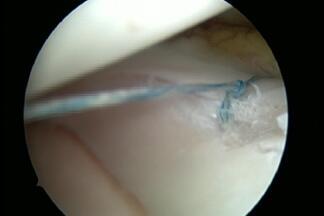

Meniscus Damage

The inner and outer meniscus serve to buffer the load and stabilise the joint. Damage to the meniscus can occur due to accidents, or wear and tear, or a combination of both. The consequences are pain, swelling, and possibly also entrapment. Meniscus damage occurs most frequently between the ages of 30 and 50. Men are affected twice as often as women (9 to 4.2/10000 respectively). If the damage is symptomatic, it can be repaired minimally-invasively by arthroscopy. The follow-up treatment depends on whether parts of the meniscus were removed (pain-adapted full weight-bearing) or whether the meniscus was sutured (usually partial weight-bearing). Unfortunately, only a few meniscus tears are suitable for suturing.